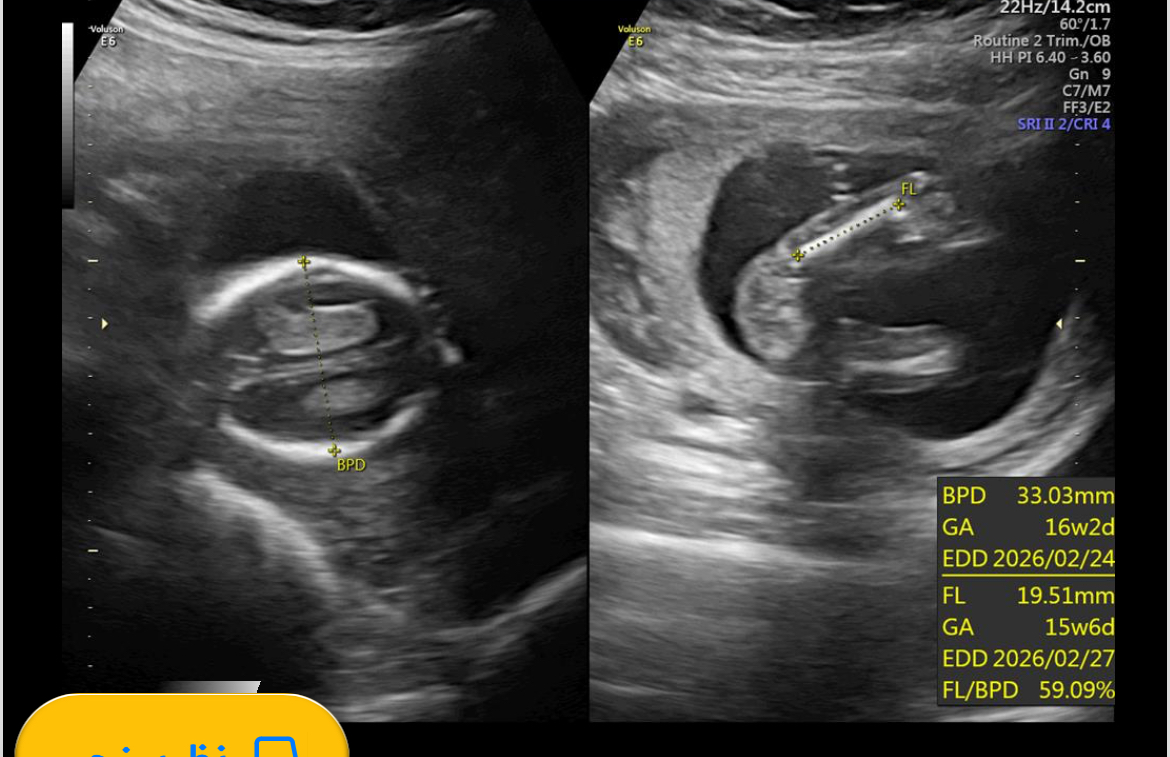

مرسی عزیزم من الان ۴ماه هستم ۱۷هفته